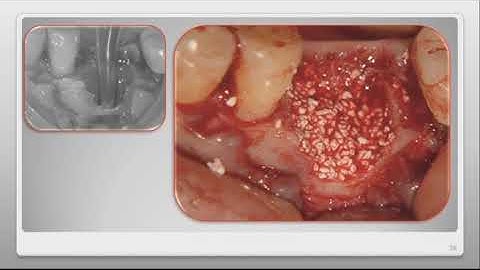

The effortless placement of R.T.R.+ Membrane